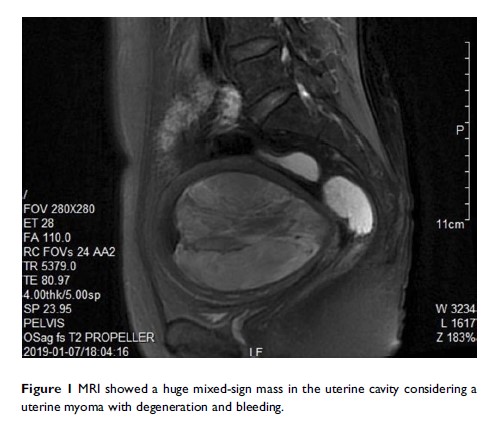

1 份子宫平滑肌肉瘤病例报告